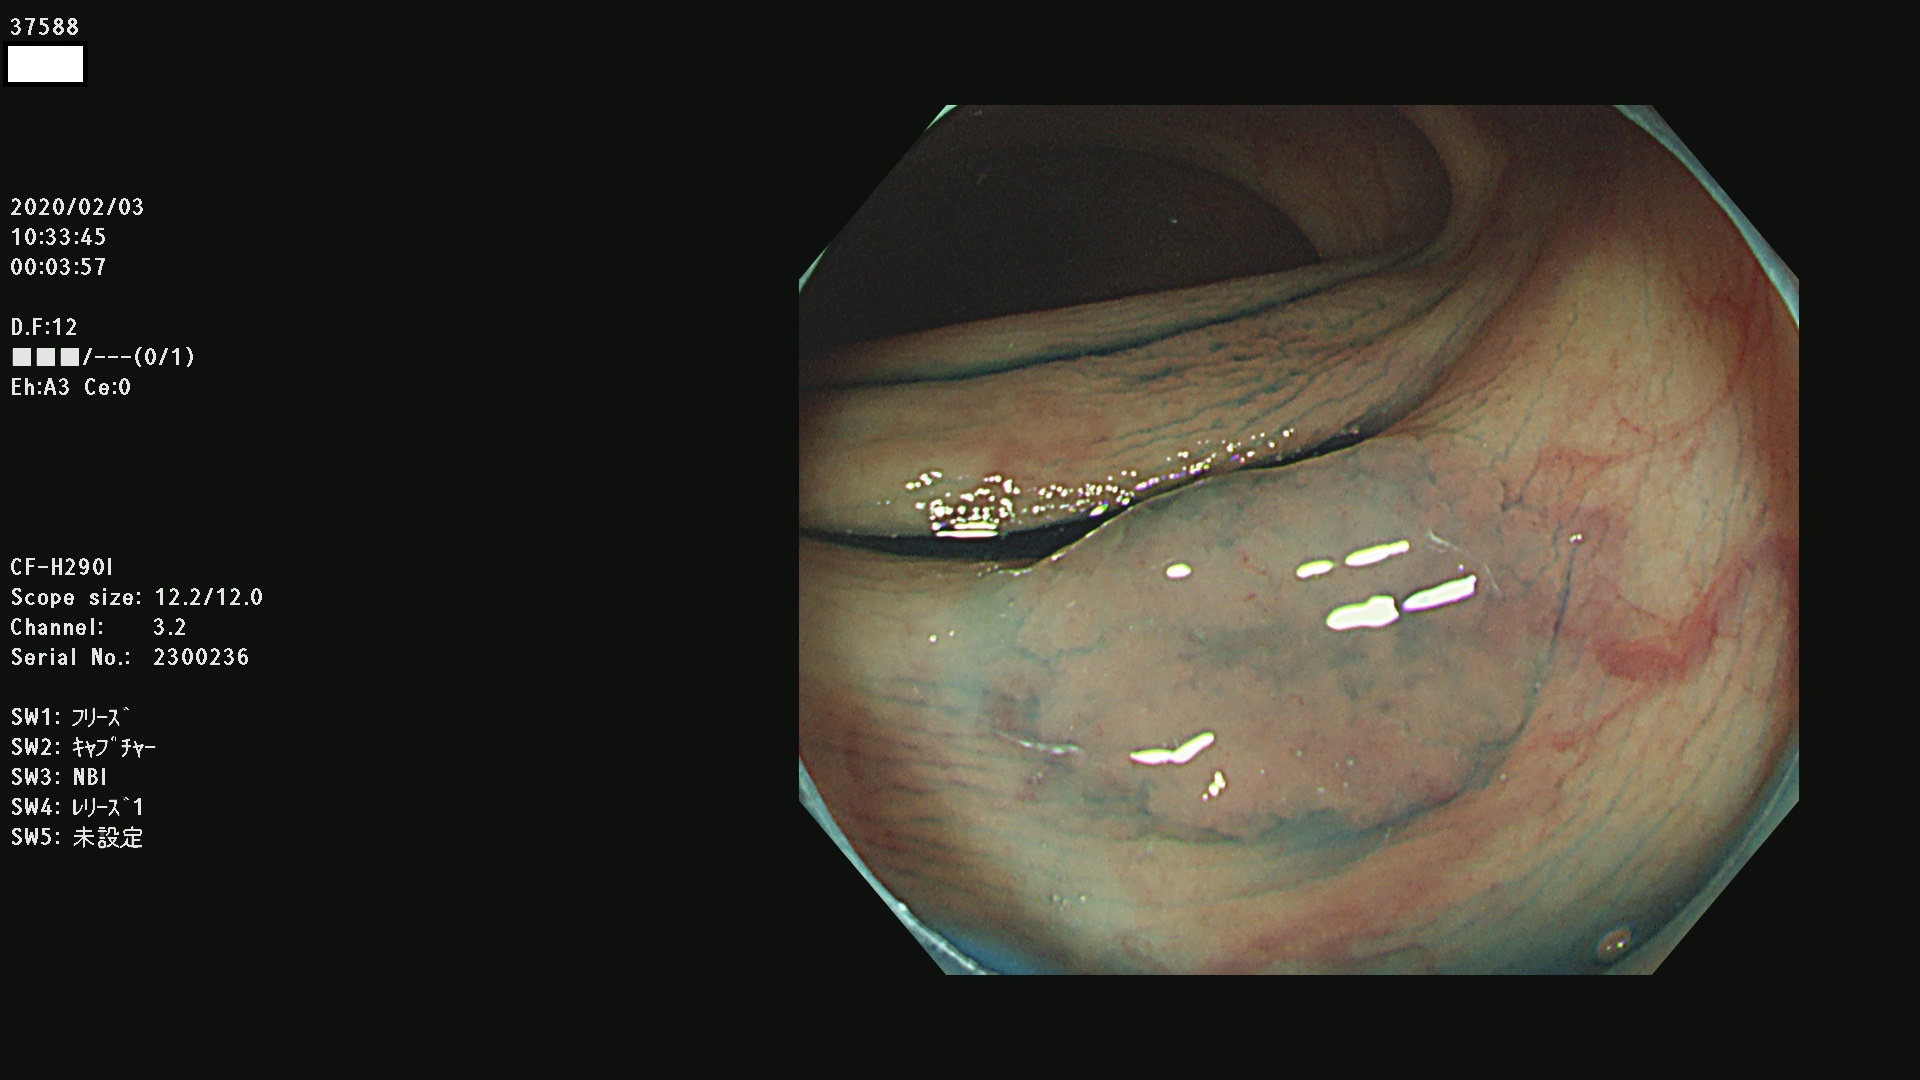

腺腫発見率 67 % (カルテ番号 37500〜37599の100名の方の検査結果で集計)大腸癌検診最新情報

以下のカルテ番号の方に腺腫(Adenoma,Group3〜5)が見つかりました(集計法)

37500 37502 37503 37505 37508 37509 37510 37511 37512 37513 37514 37517 37519 37520 37521 37525 37526(SSAPのみ) 37527 37528 37529 37531 37532 37533 37534 37536 37538(SSAPのみ) 37539 37541 37542 37543 37547 37548 37549(SSAPのみ) 37550 37552 37555 37556 37561 37562 37563(SSAPのみ) 37564 37565 37566 37567 37568 37570 37571 37572 37573 37574 37575(SSAPのみ) 37576 37577 37579 37580 37582 37583 37586(SSAPのみ) 37587 37588(SSAPのみ) 37590 37593(SSAPのみ) 37594 37596 37597(SSAPのみ) 37598 37599

発見困難で危険性の高い平坦型病変(上記100名より抽出) ![]()